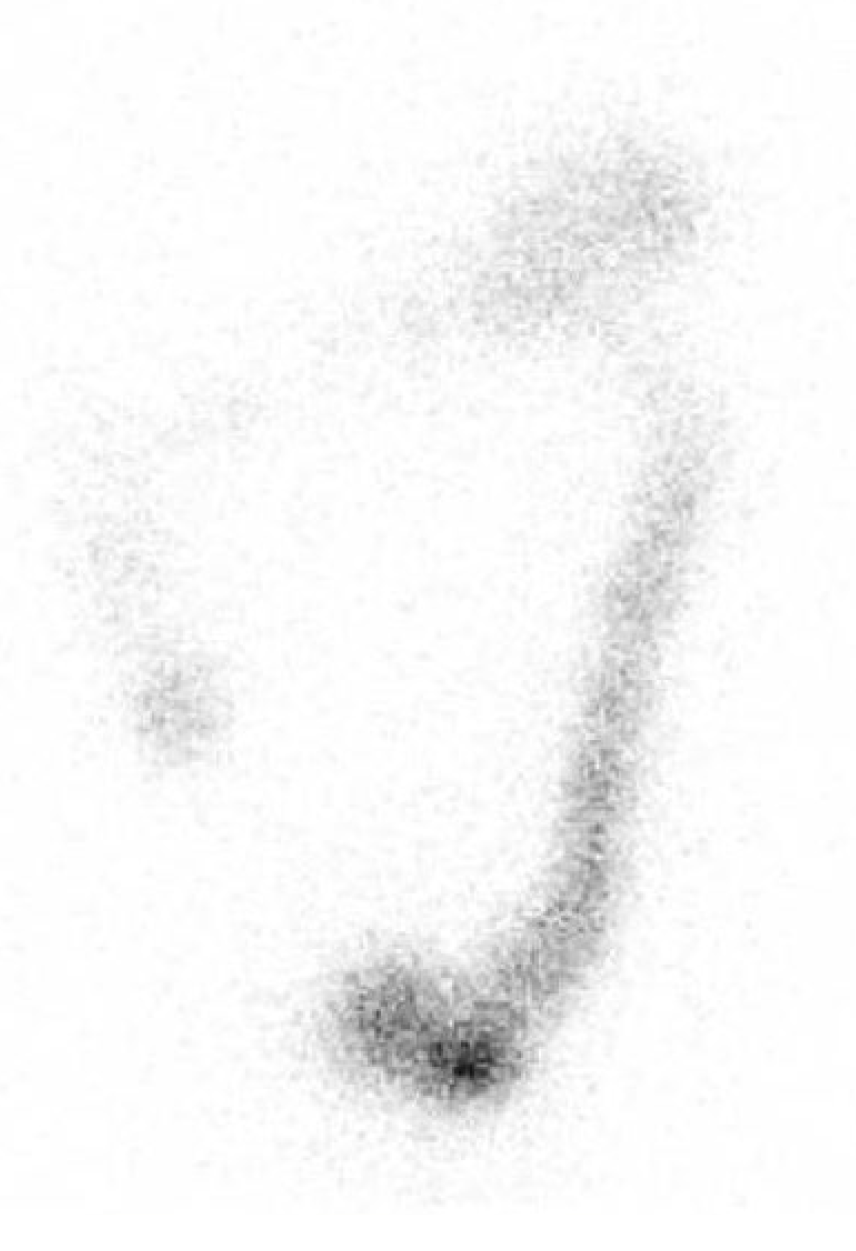

In men group of patients there was a noticeable slowing down of colonic transit in the descending colon and rectosigmoidal segment of Figure 3 and Figure 4.

Figure 4. Static scintigram in anterior projection, 48 hours after administration of radiofarmaceutical. Male 41 years old, with constipation symptomatology. Qualitatively retention of radiopharmaceutical was observed predominantly in descending and rectosigmoid part of the colon. In addition retention was observed also in ascending part of the colon. GC value was 2,3.